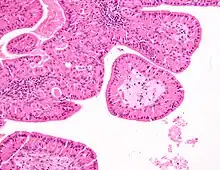

The appearance of this tumor under the microscope is unique. There are cystic spaces surrounded by two uniform rows of epithelial cells with centrally placed pyknotic nuclei. The cystic spaces have epithelium referred to as papillary infoldings that protrude into them. Additionally, the epithelium has lymphoid stroma with germinal center formation.

Low magnification micrograph of a Warthin tumor arising from the parotid gland.

Low magnification micrograph of a Warthin tumor arising from the parotid gland. -

Intermediate magnification micrograph of a Warthin tumor.

Intermediate magnification micrograph of a Warthin tumor. -

High magnification micrograph of a Warthin tumor showing the characteristic bilayered epithelium.

High magnification micrograph of a Warthin tumor showing the characteristic bilayered epithelium.